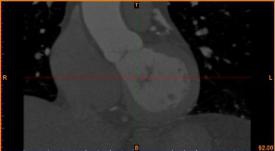

首先通過病人的心臟冠脈造影CT數據,獲取病人的心臟冠脈三維模型。

病人的冠脈造影CT數據 提取出的冠脈三維數據

其次在對應的病灶位置進行一定的細節修改,或改變其形狀或改變顏色以便于突出顯示病灶位置。